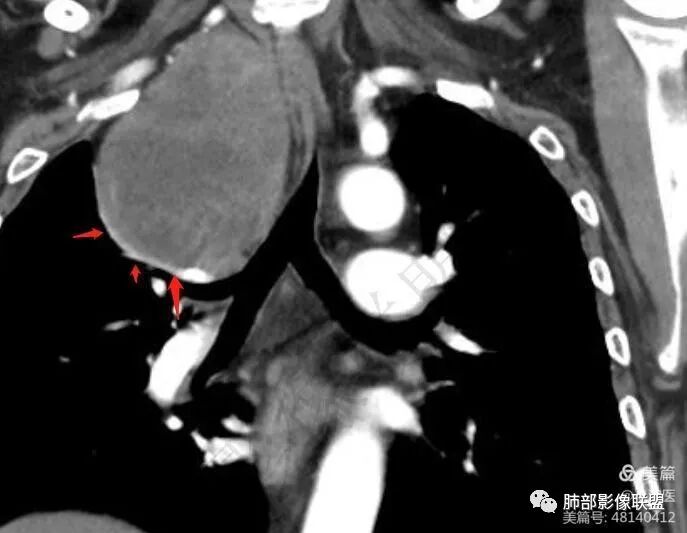

血管、压缩肺组织病灶的长轴:上下走形

推压血管,进入颈部

南边:支持:神经源性,从病灶的形态突入颈部,跨多区域

1. 右上胸廓入口区类椭圆形块影,边界清楚光整,纵向“嵌顿”于颈根部及上纵隔,向上推移右锁骨下动静脉,向外下方推移上肺胸膜及肺组织(肺血管、支气管),向前推移上腔静脉,界限清楚。

3.而“A/B”区密度特点以及上下径较大更支持神经鞘瘤,尽管这不属于好发部位。

神经鞘瘤是周围神经最常见的肿瘤,起源于神经鞘膜的施万细胞,生长缓慢,包膜完整,与起源神经紧密相连,绝大多数为良性,恶性罕见;纵隔内神经源性肿瘤90%发生于后纵隔,发生在交感神经链或肋间神经的椎旁;偶尔,神经鞘瘤可位于中纵隔或前纵隔,最常见的发生于迷走神经,其次是喉返神经、膈神经等。所以神经源性肿瘤很重要一点在于解剖,一般只要存在神经组织,都可以发生神经源性肿瘤;后纵隔神经鞘瘤最常见的位置是脊神经刚出椎间孔的位置,并沿着肋间神经分布,所以一般横径大,上下径小,而且来源于神经根的可呈哑铃状跨越椎管内外生长;而来源于前或中纵隔神经的迷走神经或喉返神经等是上下走形,所以神经鞘瘤常表现为上下径长;神经鞘瘤在病理上包括A区和B区,Antoni A区富含细胞,密度较高,Antoni B区含有较多粘液成分,密度较低,可见囊变、出血,如果出血,血肿可见机化、钙化。

中纵隔迷走神经走形

中纵隔右侧迷走神经来源神经鞘瘤

中纵隔神经鞘瘤(迷走神经走形,上下径大于左右径)